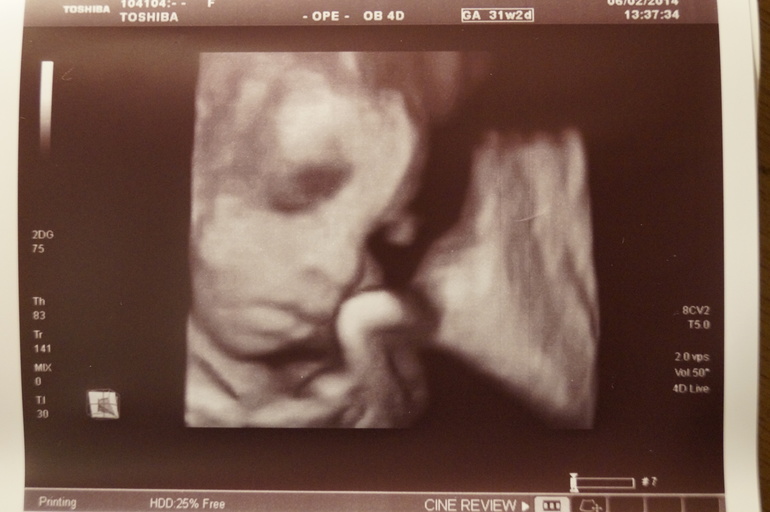

Дальше наша милашка!

Дочка у нас будет жизнерадостной и весёлой! Врач опять смогла запечатлеть нашу очаровательную улыбочку!!!!